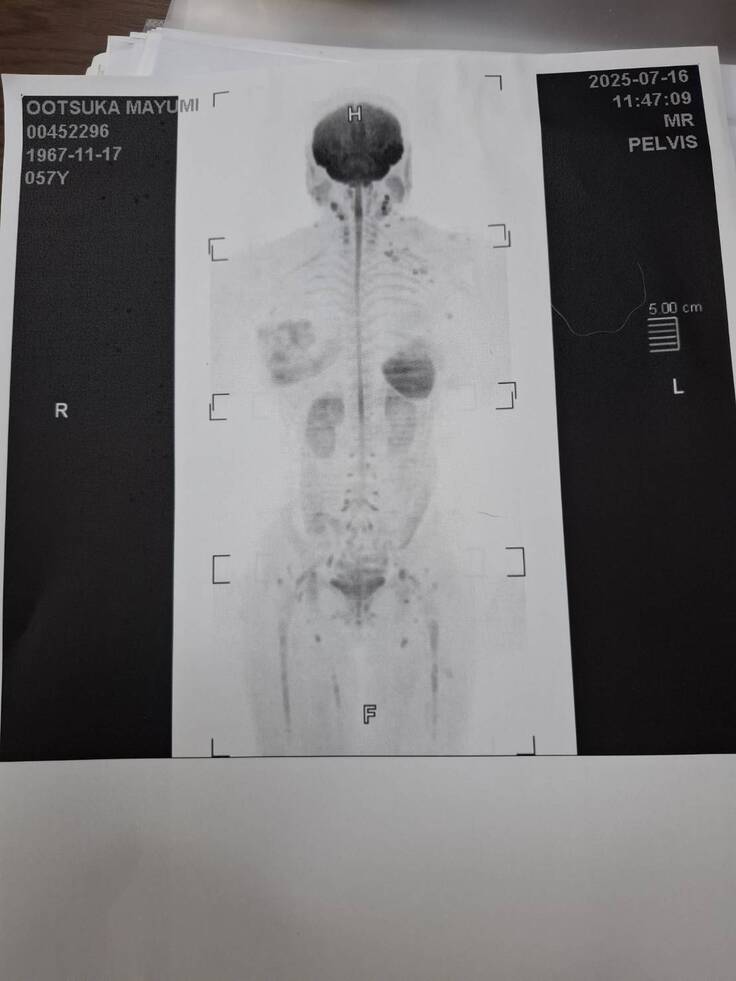

私のほうは、ちょっとグロテスクな画像で申し訳ありませんが

MRIの結果、再発、転移は今のところありませんでした。

ほっとしました💦

次は昨年、手術をした1年後、今年の11月にまた検査をする予定です。

私のMRI検査結果です